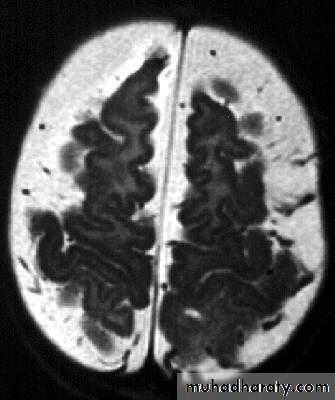

Bacterial Meningitis with cerebral oedema